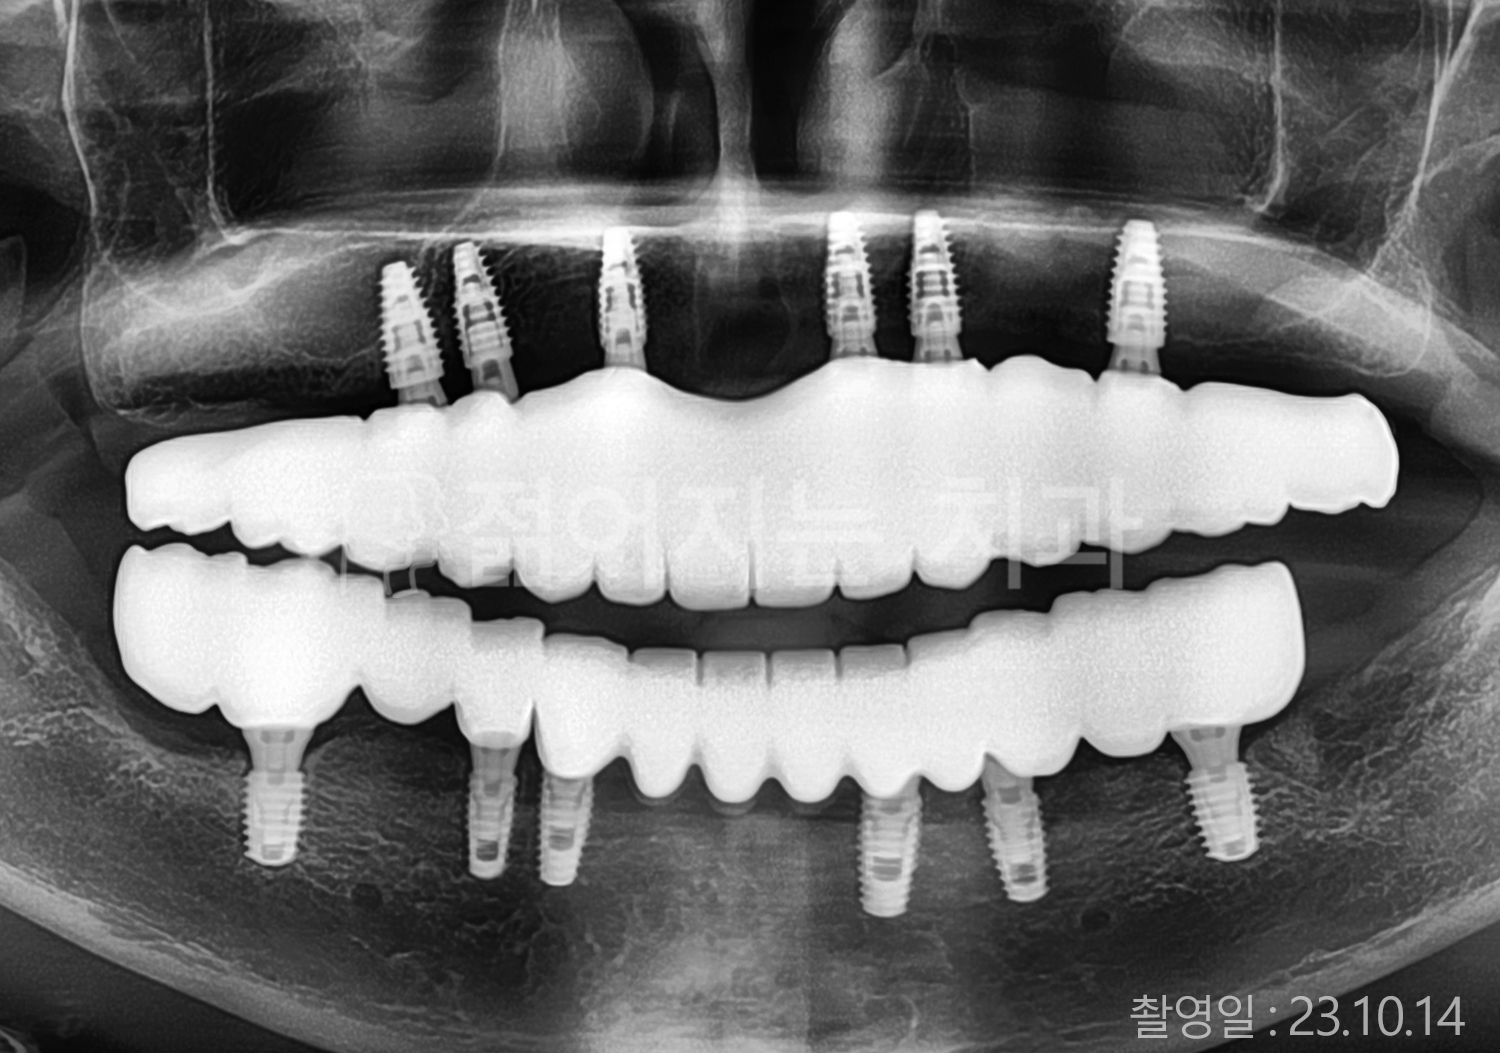

• 50대 고혈압, 당뇨, 고지혈증 전체치아 10개 이상 임플란트

• 60대 골다골증, 간경화 전체치아 10개 이상 임플란트

• 60대 고혈압, 고지혈증 전체치아 10개 이상 임플란트

• 50대 고혈압, 당뇨 전체치아 10개 이상 임플란트

• 60대 고혈압 전체치아 10개 이상 임플란트

• 60대 전체치아 10개 이상 임플란트